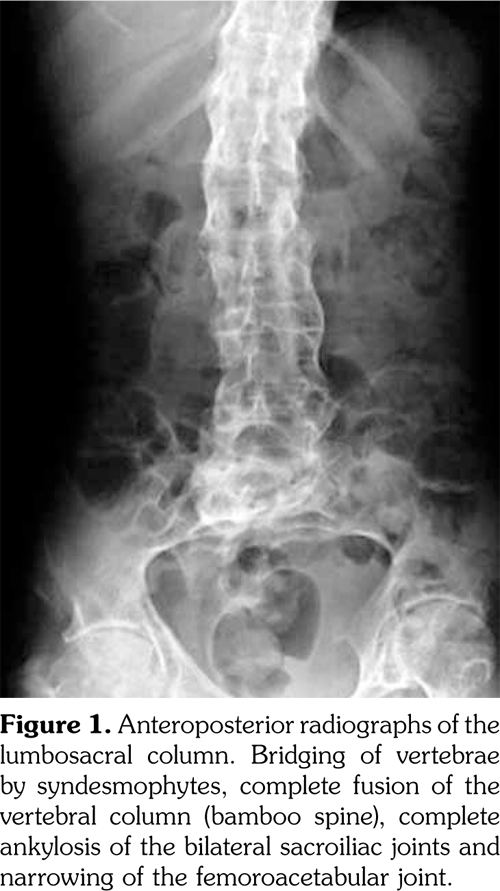

Laboratory assessment before the surgery demonstrated the erythrocyte sedimentation rate as 55 mm/h and C-reactive protein as 43.7 mg/L. Hepatitis markers and Brucella agglutination test were negative. The lumbosacral MRI which was performed before the surgery detected edema at the L3 vertebral corpus, oblique fracture at the L3 vertebral corpus, and 75¥13 mm epidural hematoma through the L1-L3 vertebrae (Figure 3, 4). After the epidural hematoma drainage and decompression surgery, the patient was transferred to the physical medicine and rehabilitation inpatient clinic for the rehabilitation program.